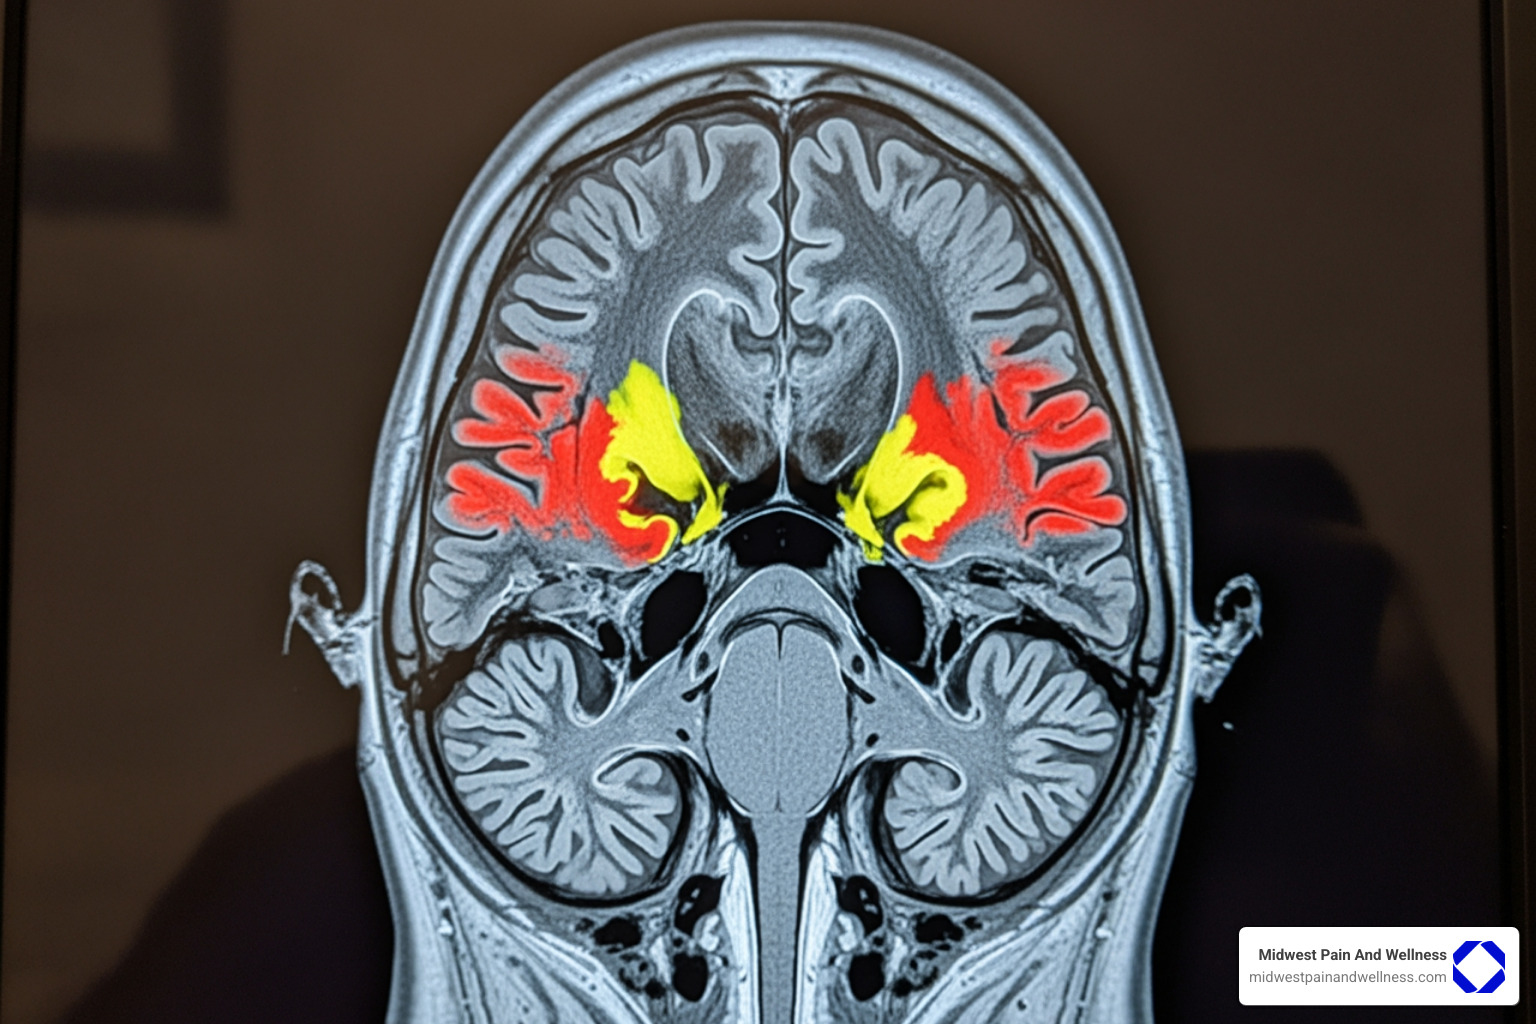

While opioids can offer strong pain relief, they come with a long list of serious risks. They work by slowing down your central nervous system, which can lead to life-threatening respiratory depression (slowed breathing). They also carry a high risk of addiction and dependency. Opioids can change your brain’s reward system, and the body can become physically reliant, leading to withdrawal. You can learn more about these changes in the brain that contribute to addiction.